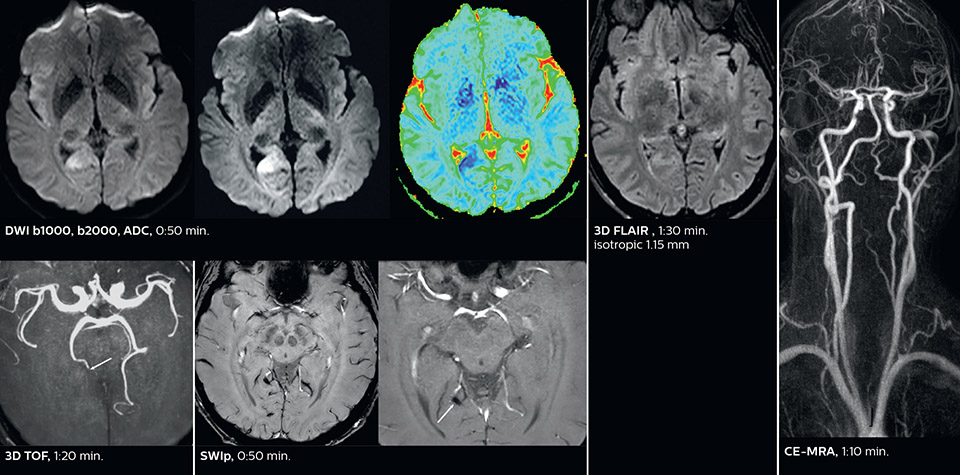

The ability to perform more sequences can help in making a swift and confident diagnosis. “For example, our stroke cases usually include the regular sequences that every center does (b1000 diffusion, FLAIR, time-of-flight angiography), but we also image supra aortic vessels, and we can replace a gradient echo sequence with a fast 50-second susceptibility-weighted sequence, and all of this doesn’t add much time. because all the regular sequences are accelerated on Elition.”

Using MultiBand SENSE allowed the staff to improve their diffusion quality. “Our diffusion sequence was already fast before, about 40 seconds. Now with Elition, it still lasts 40 seconds, but we improved the spatial resolution by 0.2 mm and use high b-values to be more sensitive to visualize changes related to acute stroke,” says Dr. Savatovsky.

Fast acute stroke protocol

This is an example of acute ischemic stroke with distal occlusion of the right posterior cerebral artery. Note the improved visibility of the ischemic territory on the diffusion weighted image with high b-value. The 3D FLAIR shows a distal PCA occlusion. The fast SWIp depicts the thrombus on the isolated second echo image. The total scan time (including SmartBrain, preparations and a fast 3D T1w TSE Gd) is 8:00 minutes.